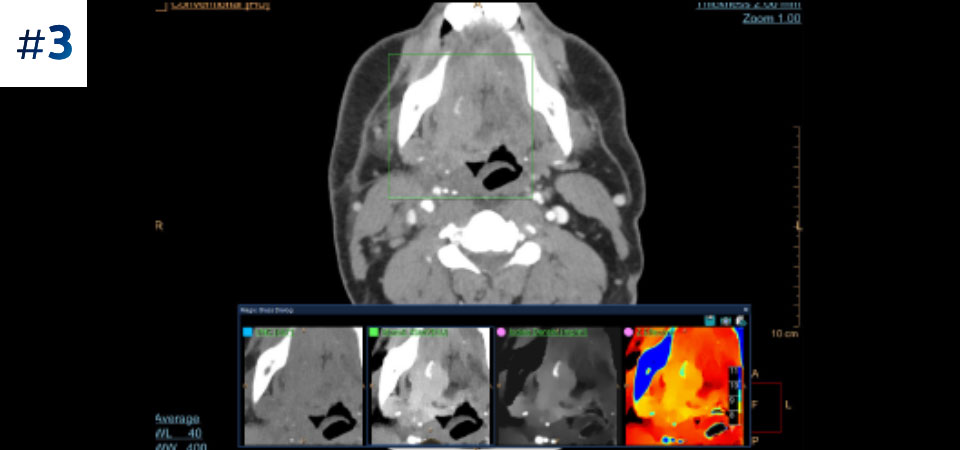

Neck mass

With detector-based spectral, you acquire multiple layers of data—conventional and spectral—within a single exposure and without special scan modes for improved tissue characterization and visualization.

Reduced follow-up exams Improved tissue characterization and visualization may reduce the need for follow-up scanning for sub-optimal exams and incidental findings.